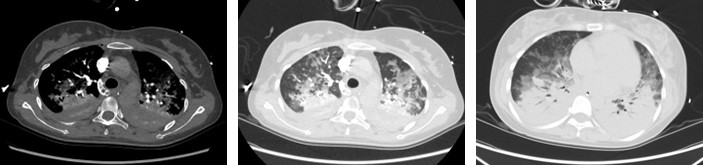

6月6日,呼吸机辅助下外出行肺动脉CTA检查确诊肺动脉栓塞。患者羊水栓塞后DIC、肺部感染、ARDS肺水肿,血红蛋白低至57g/L,并导致多脏器功能损伤。经全院MDT多学科讨论和EICU边圆教授团队积极抗感染、机械通气、CRRT血液滤过、输血及抗凝等治疗后,患者肺部情况较前改善,感染指标下降。成功脱机拔管,序贯无创呼吸机及经鼻高流量湿化氧疗,患者病情好转后转回产科继续治疗。

胸部CTA强化显示:肺动脉栓塞、肺部感染炎症、肺水肿与肺不张